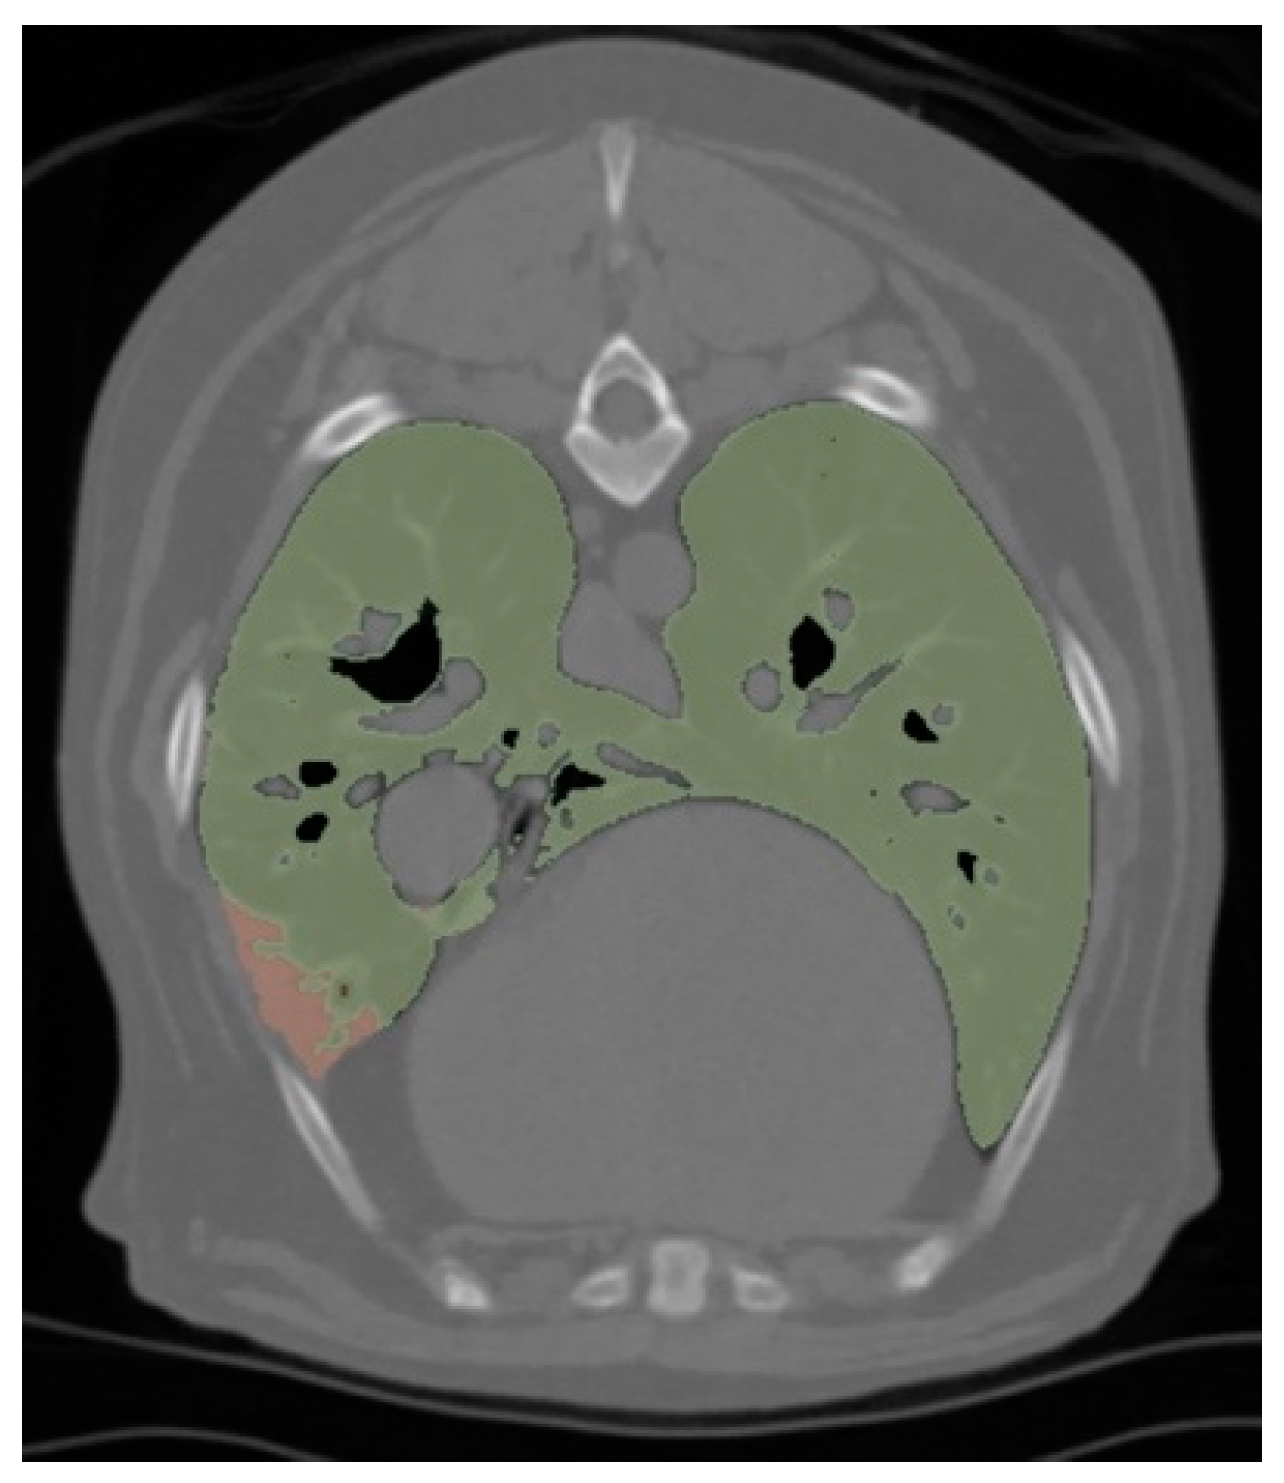

| Non-Aerated Lung Volume (NLV) (cm3) | 3.66 (IQR = 1.11–5.47) | 1.49 (IQR = 0.39–2.60) | 0.02 |

| NLV/Body Weight (cm3 kg−1) | 0.14 (IQR = 0.09–0.22) | 0.10 (IQR = 0.02–0.13) | 0.03 |

| Aeration (%) | 99.68 (IQR = 99.53–99.79) | 99.82 (IQR = 99.68–99.96) | 0.01 |

| Number of Lobes with Atelectasis | 2.00 (IQR = 1.00–3.25) | 1.00 (IQR = 1.00–2.00) | 0.16 |